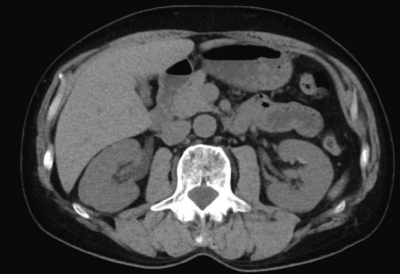

尿所見:蛋白(-)、糖(-)、潜血3+、沈渣に赤血球 100 以上/1視野、正八面体の結晶を認める。血液所見:赤血球 458 万、Hb 14.0 g/dL、Ht 45 %、白血球 9,300、血小板 21 万。血液生化学所見:総蛋白 7.2 g/dL、アルブミン 3.7 g/dL、総ビリルビン 0.9 mg/dL、直接ビリルビン 0.2 mg/dL、 AST 35 U/L、ALT 32 U/L、LD 179 U/L(基準 176〜353)、尿素窒素 22 mg/dL、クレアチニン 1.2 mg/dL、尿酸 6.9 mg/dL、血糖 98 mg/dL、Na 132 mEq/L、K 4.3 mEq/L、Cl 97 mEq/L、Ca 9.1 mg/dL。非ステロイド性抗炎症薬が投与され痛は軽減した。その後に撮影した腹部CT を示す。